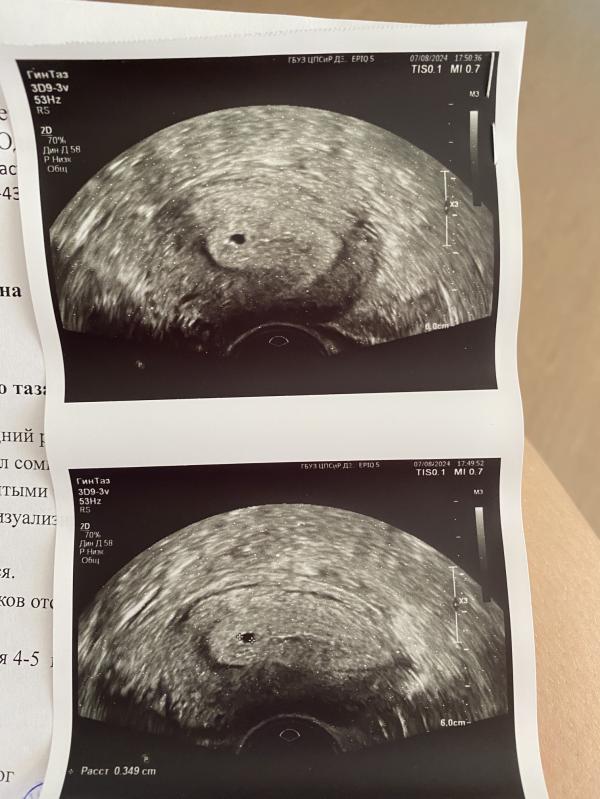

В матке плодное яйцо увидели, но маленькое, ре говорит где то на неделю отстает , 20 дпп сегодня.

Эмбриона и желтого мешочка пока не видно, но главное что маточная беременность.

Хгч в пт был 1014 , сегодня еще раз сдам